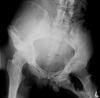

What is the most likely diagnosis? What bones are involved?

AVN of femoral head